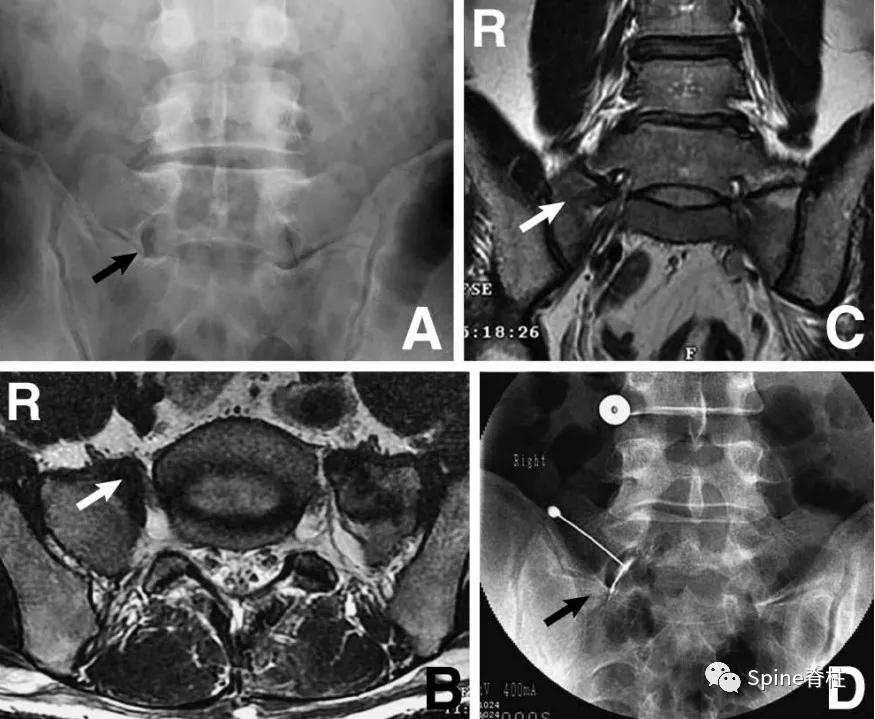

图示:确诊为 LSTV IIb型(具体分型详见: 你注意过腰5椎体的横突吗? ),患者L5神经根右下肢放射痛通过选择性根管造影确诊,增生肥大的横突与骶骨形成的假关节压迫椎间孔外侧远距离处的L5神经。